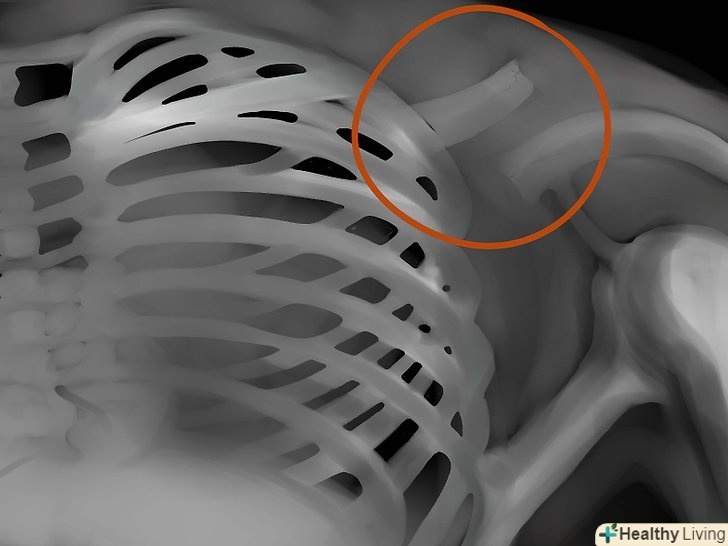

Кістки. уважно подивіться, чи немає де пошкоджень і травм кісток. Розмір, форму, контур і колір кісток необхідно примітити - все це цінний діагностичний матеріал, на підставі аналізу якого можна виявити безліч захворювань і патологій.

Інструменти.всі трубки, водії ритму, хірургічні затискачі, дренажі, імпланти - все це треба знайти.